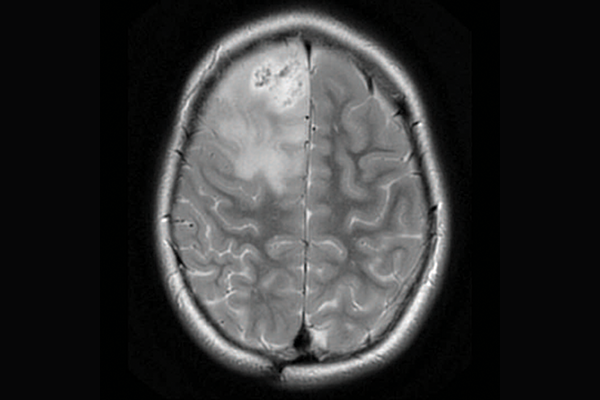

Brain scans showing three different subtypes of priMMRD high-grade glioma.

A scan of a brain with priMMRD subtype 2

priMMRD-2: The double agent

These tumours account for 19 per cent of the gliomas studied and have MMRD mutations without PPD or IDH1 gene alterations. For these patients, a single-agent immunotherapy is less effective, but adding a second agent may improve outcomes. The OPTIMISE trial, led by Dr. Daniel Morgenstern at SickKids, is using an adaptive trial design to target these specific genetic variations.